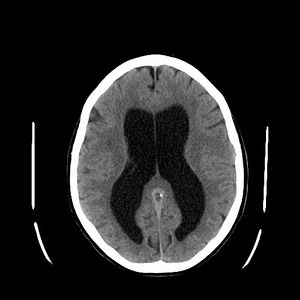

| استسقاء المخ كما يظهر في الأشعة المقطعية على المخ. المناطق السوداء في منتصف المخ هي تضخم غير طبيعي ومملوء بالسوائل. | |